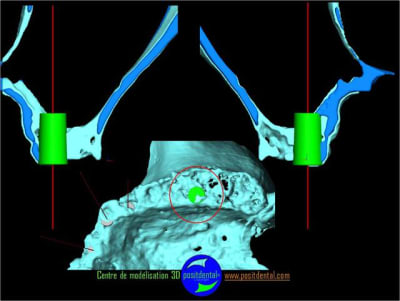

Expansion, condensation guidée

votre avis sur ce cas clinique

suite

Pose d’un implant au maxillaire dans une zone de faible densité

précision de la chirurgie guidée condensée

Le guide chirurgical, positionneur d’implants reste en place jusqu’à la pose des implants.